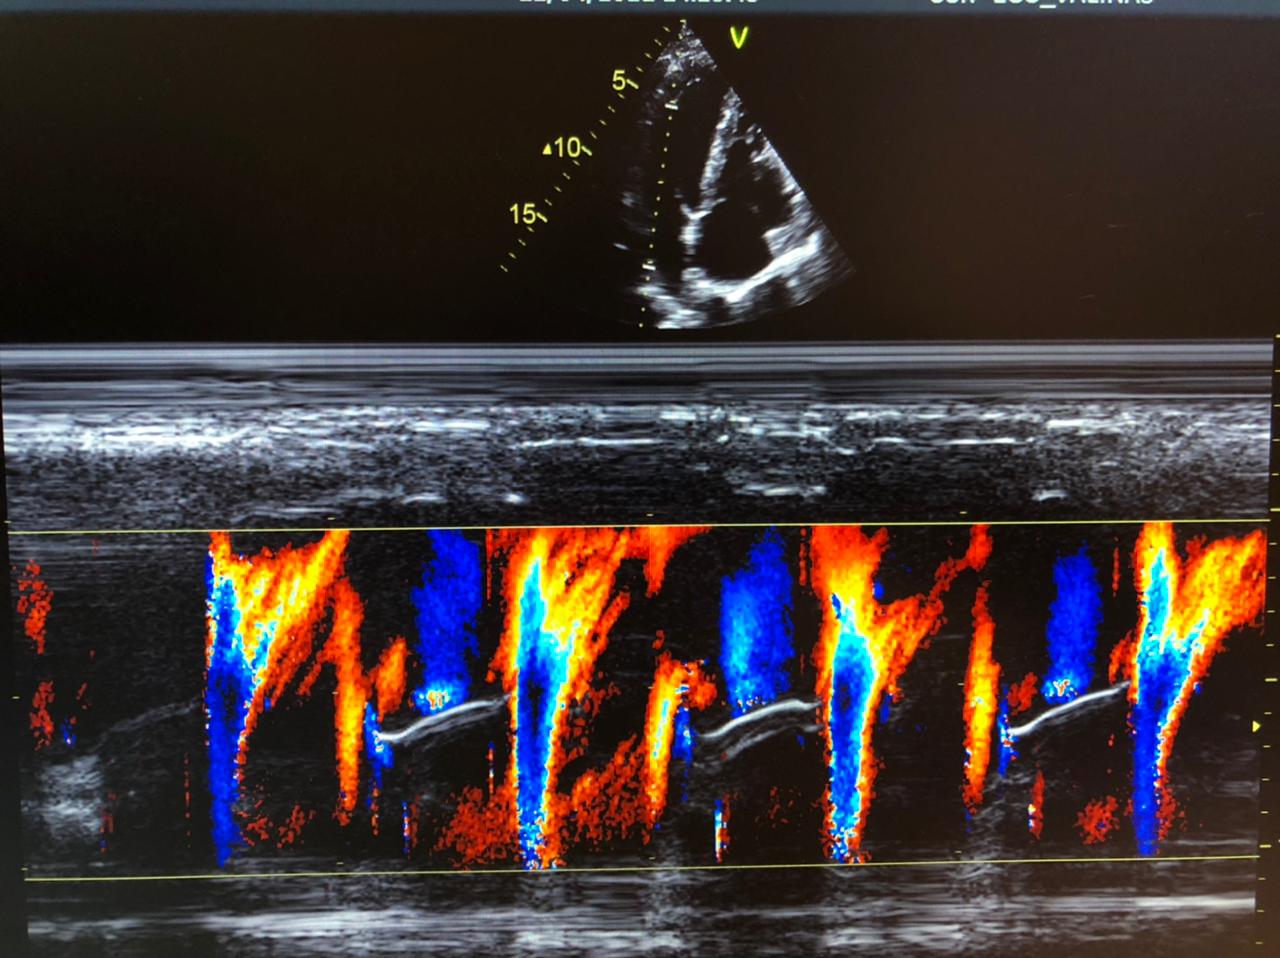

Quando o médico precisa de dados mais específicos sobre o fluxo de sangue e sua circulação pelas veias e artérias, é utilizado o ecocardiograma com doppler colorido.

As cores mostradas no exame ajudam a ter detalhes completos sobre a direção e a velocidade da circulação.